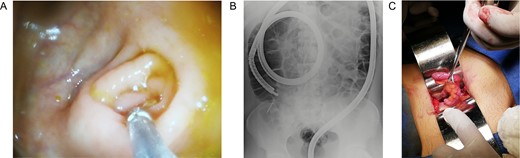

(A) Completely resected appendix. (B) Appendix and metallic nail.

In this context, a surgical approach was needed to assess the appendix and the cecum wall. After a Rocky-Davis incision, the appendix was exposed and an object of hard consistency was found at its tip (Fig. 3B). The surgical decision was straightforward, the appendix was resected, and the surgery was completed without complications (Fig. 1C).

After this, the appendix was dissected and a 30 mm nail was found inside its lumen (Fig. 2C and Supplementary Video).